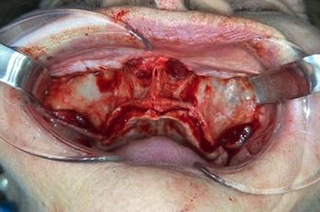

Estructura Subperióstica con carga inmediata maxilar

Paciente con atrofia total del hueso del maxilar que precisa rehabilitación. Se le realizó tratamiento con estructura subperióstica y el mismo día se le colocaron unos dientes fijos provisionales sobre la estructura.